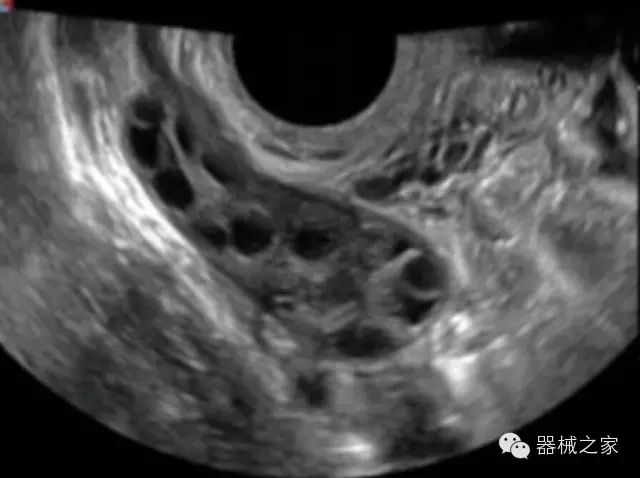

臨床圖片賞析

·亞陣元技術(shù):獨(dú)有的亞陣元技術(shù),對(duì)獨(dú)立晶片做二次切割,減少旁瓣偽像,增加臨床診斷的準(zhǔn)確性;

·μ-Scan微米成像技術(shù):開立獨(dú)有的μ-Scan技術(shù),還原出真實(shí)細(xì)膩、層次對(duì)比優(yōu)異的二維圖像;

·倒相諧波成像技術(shù):倒相諧波技術(shù)在去除基波信號(hào)的基礎(chǔ)上獲取兩倍二次諧波信號(hào),提高組織圖像的對(duì)比分辨力;

·智能微血流成像技術(shù):智能微血流捕捉技術(shù)可以提取出隱藏在背景噪聲中的弱血流信號(hào),大大提高低速血流的敏感性;

·獨(dú)有的大角度及實(shí)時(shí)溫控技術(shù),能同一切面顯示宮頸及宮體,有效減低了患者的痛苦,及保護(hù)粘膜保證了醫(yī)療安全;